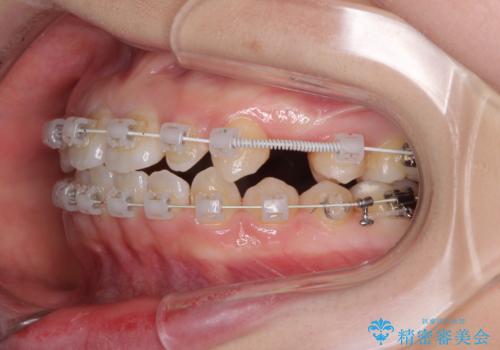

- 歯の欠損による隙間だらけの歯並びを気にして来院された患者様です。

上顎左右1本ずつ欠損していたため、歯列矯正により欠損部位にスペースを集め、その後欠損部位をインプラントにて補綴することとしました。

インビザラインによる矯正治療も提案しましたが、長時間の装着や自己管理が難しいとお考えで、ワイヤーによる矯正治療を行いました。

歯並びは比較的早めに整いましたが、インプラントを埋入するにあたって前後の歯根位置を改善する必要があり、矯正治療に期間を要することとなりました。